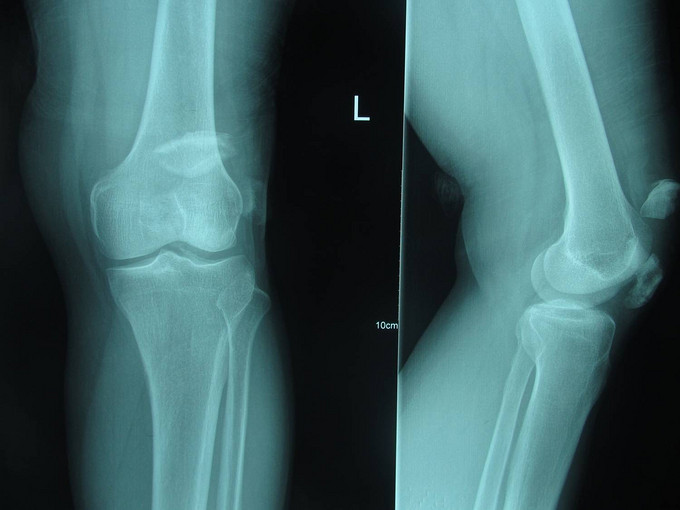

患者自诉于2015年5月17日晚21点多在外不慎摔伤,致左膝部疼痛肿胀活动受限,当时无意识不清,急诊送当地医院(铁岭市中心医院),行左膝关节DR及三维CT:左髌骨骨折。今为进一步治疗急于我院中国医科大学附属盛京医院,行X线片检查示:左髌骨骨折,急诊以“左髌骨骨折”为诊断收住入院。

专科查体:患者轮椅入病房,左膝部肿胀明显,疼痛,压痛(+),活动受限,骨擦音,骨擦感(+), 患肢足趾活动可,足背动脉可触及。

诊断:左髌骨骨折 患者入院后左膝部抬高,冷疗,消肿等对症治疗后,约一周后行左髌骨骨折切开复位张力带内固定术。